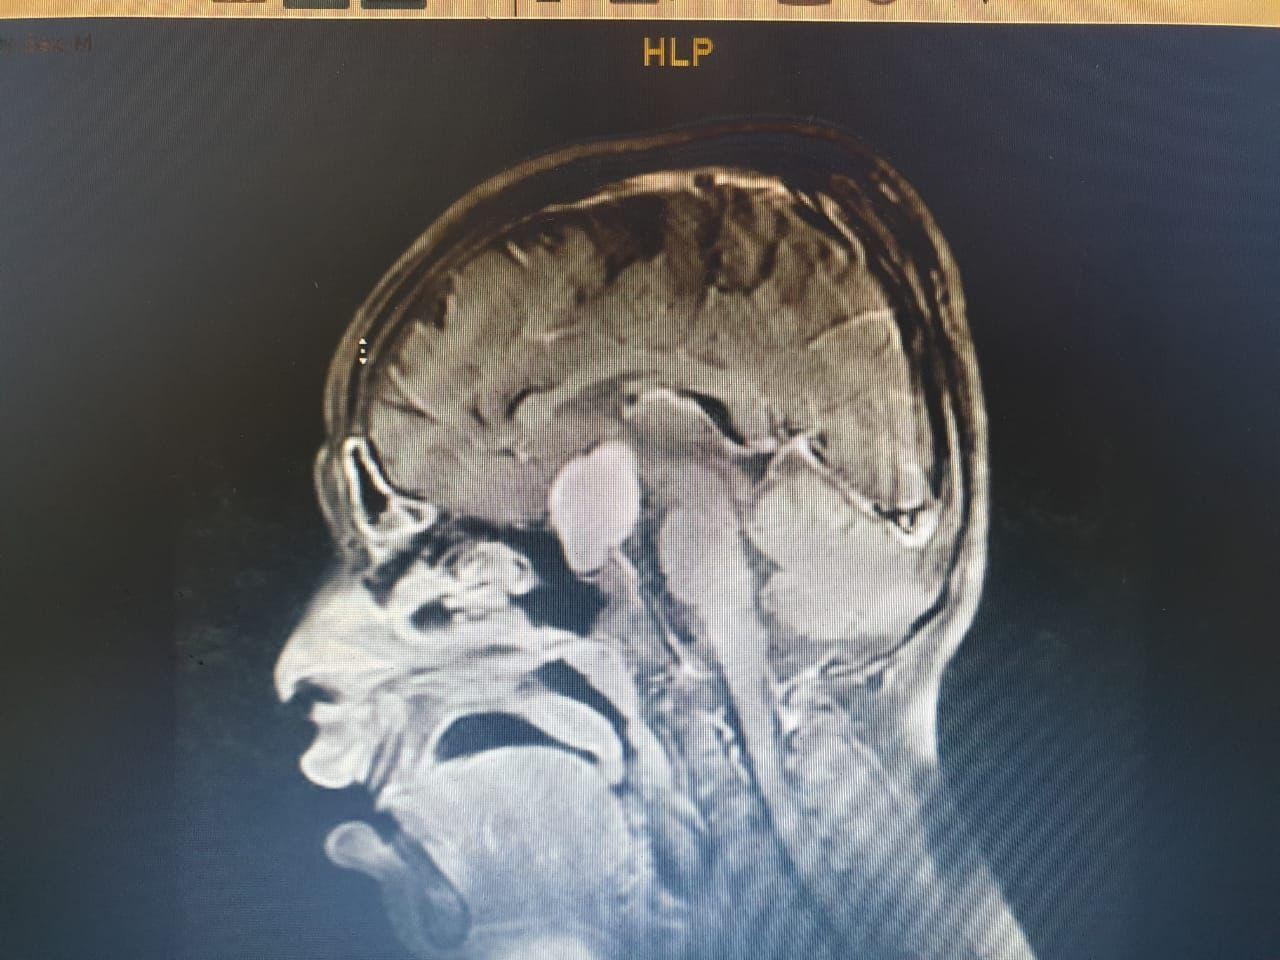

وعلى الفور أجرى الفريق فحوصات متقدمة ، واتضح وجود"ورم" بقاع الجمجمة ، ومتصل بالغدة النخامية.

وأشار المتحدث الرسمي بصحة الطائف سراج الحميدان ,أن الفريق الجراحي للمخ والأعصاب ، تدخل جراحيا بعملية استمرت 7 ساعات لإزالة الورم بالرغم من خطورة الوضع ، وتكللت بالنجاح بفضل الله .